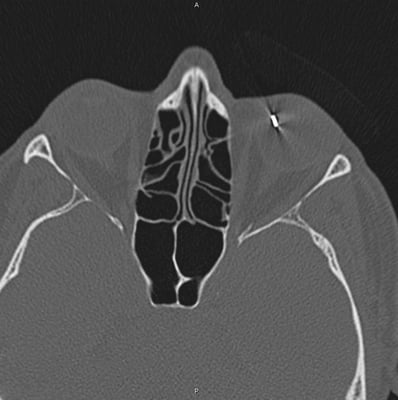

links: Computertomographie mit metallenem Fremdkörper im Auge, rechts: Metallfremdkörper nach Entfernung aus dem Auge